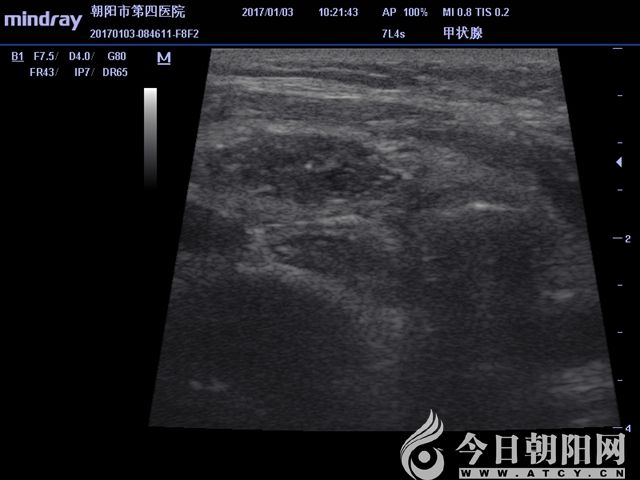

超聲顯示囊實(shí)結(jié)合性病變

超聲下病變顯示